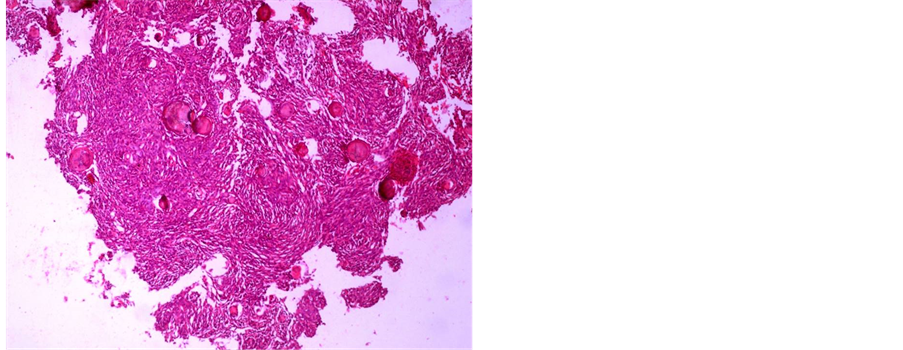

A 61-year-old female patient was with history of spinal trauma in 26 year ago. Patient fall down from height and had a traumatic L1 fracture. Patient was managed conservatively at that time as she refused surgical intervention and had no neurological deficit. Patient experienced frequent attacks of low back pain and rarely sciatic pain that was treated with analgesia. 6 months ago, the patient had a progressive heaviness in both lower limbs with urinary incontinence and visited the outpatient clinic. On examination, the patient was paraparetic with motor power grade II or III below L1. Patient had hypotheisa below L1 with diminished knee and ankle reflexes. MRI lumbar and dorsal spine showed the post-traumatic L1 fracture with a new large intra-dural mass most probably meningioma or schwnoma as shown in Figure 1. Patient operated with posterior lumbar approach including posterior L1 and D12 laminectomy. Total standard microscopic excision of the intra-dural soft tissue mass with moderate vascularity was performed successfully. A posterior D11, D12 and L2 trans-pedicular screw fusion was performed at the end of the procedure. Histopathological examination revealed multiple nodules of proliferated meningothelial cells separated by delicate fibrous tissue, with thick walled blood vessels and calcified psammoma bodies together with oval to rounded cells with oval nuclei, occasional nuclear clearing and infrequent mitosis arranges in whorly pattern with rounded calcified psamma bodies. A meningeothelial and psamomatous meningioma was reported as shown in Figure 2. The patient has smooth postoperative course with improvement of her neurological deficit with physiotherapy. 4 months after surgery, the patient was able to ambulate without assistance. On her last follow up after one year of surgery; the patient has no neurological deficit and can ambulate without assistance

Figure 2. (a) Photomicrograph showing multiple nodules of proliferated meningothelial cells separated by delicate fi- brous tissue, with thick walled blood vessels and calcified psammoma bodies, H & E × 40 (b) and (c) Photomicr- graph of meningioma showing oval to rounded cells with oval nuclei, occasional nuclear clearing and infrequent mi- tosis arranges in whorly pattern with rounded calcified psammoma bodies, H & E × 400.